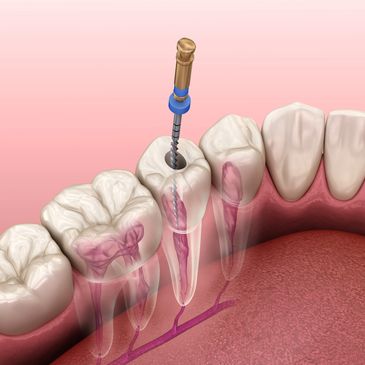

Kanal tedavisi (endodonti), çok hasar görmüş veya enfekte olmuş bir dişi çekmek yerine, dişi kurtarmak için yapılan bir tedavidir. Dişin en iç dokusu olan pulpa yani sinir ve damar doku dişten sökülür, dişin içi temizlenip, dezenfekte edilir ve oluşan boşluğu kapatmak için dişe dolgu yapılır. Her dişe kanal tedavisi uygulanabilmektedir. Dişin enfeksiyon kaptığı durumlarda ve etkilenen kanal sayısına göre tedavinin süresi uzayabilmektedir.